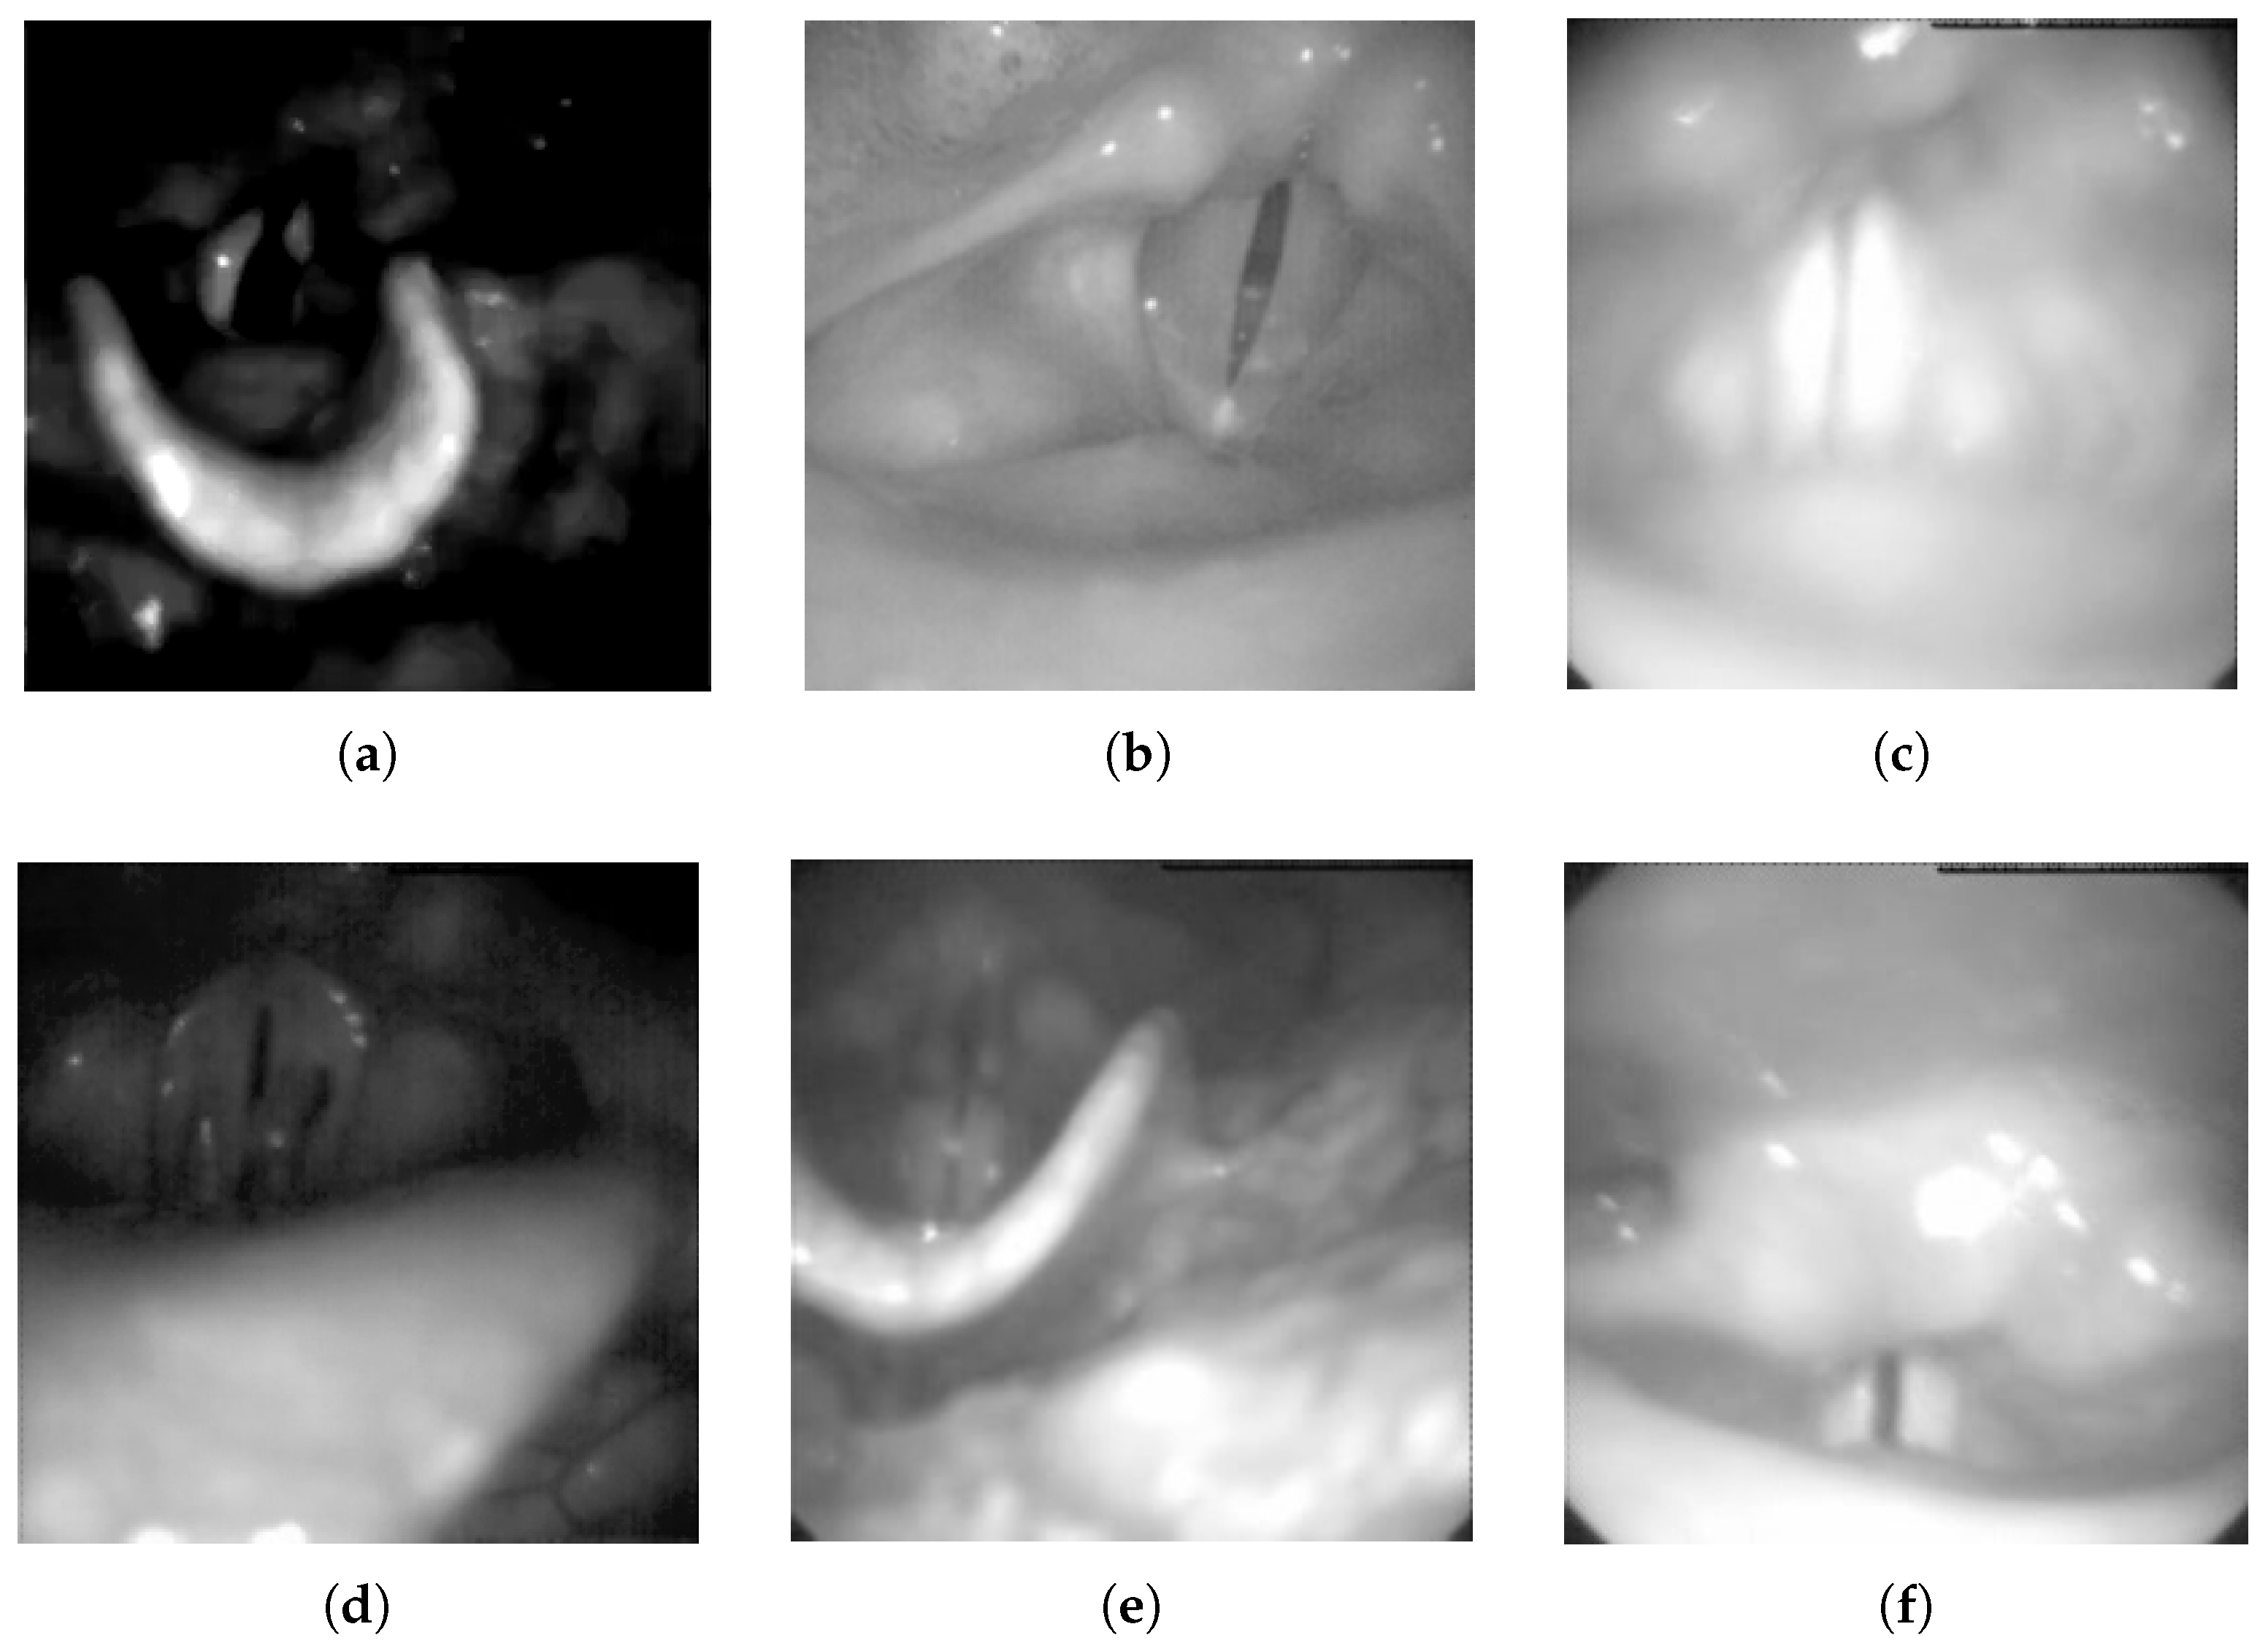

2. Laryngeal Image Modalities

2.2. Laryngeal High-Speed Videoendoscopy